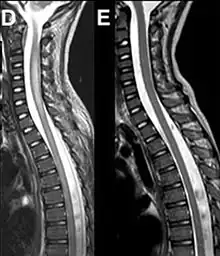

| Magnetic resonance imaging of the spinal cord in a case of AFM showing cord swelling in (d) which has resolved three weeks later in (e).[2] | |